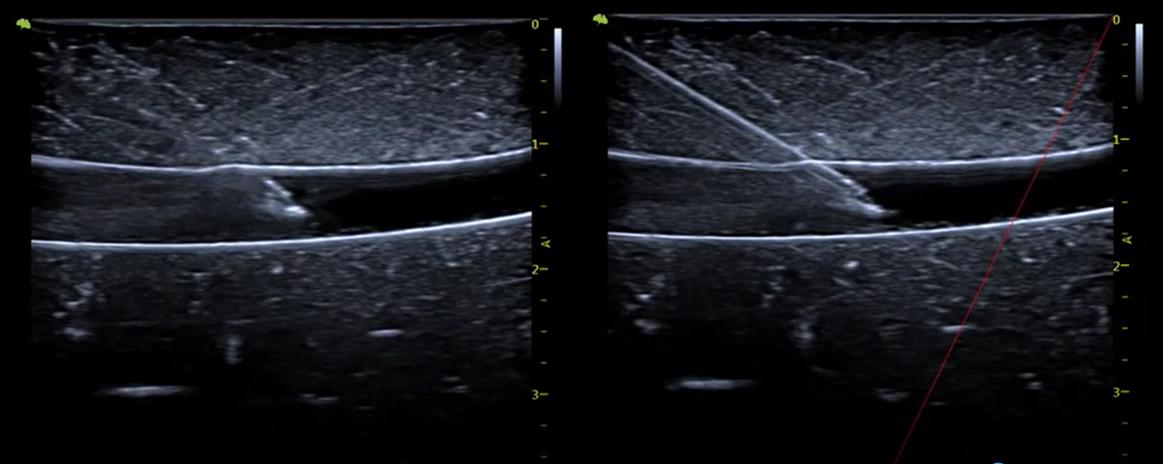

6. Vis needle Tăng cường khả năng hiển thị và độ chính xác cho các thủ thuật được hướng dẫn bằng siêu âm. Một phương pháp đặt kim đơn giản với khả năng quan sát kim tốt hơn để định vị và nâng cao độ chính xác cho các thủ thuật được hướng dẫn bằng siêu âm.